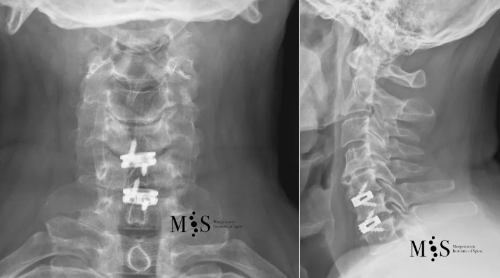

Post-operative X-rays showing an interbody cage at two separate cervical disks after placement with endoscopic fusion surgery

of the cervical spine and was discharged from the hospital in less than 24 hours after surgery.

X-ray in A/P (left figure) and lateral (right figure) figures of a titanium

interbody cage placed at level C5/C6 with endoscopic surgery

This 49 years-old patient presented with a migrated cervical herniation at level C4/C5 and an unstable disk at C5/C6. En endoscopic cervical decompression was performed to remove the herniation and two intervertebral cages were placed endoscopically using a a skin incision of just 2 cm length. Post-operatively, the patient recovered very quickly and was discharged from the hospital within a day after surgery.